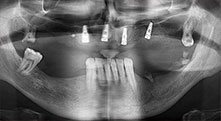

Implantes

Los cuatro implantes se encuentran in situ tal como estaba planeado. Los molares distales del maxilar superior sirven además para fijar la prótesis con base reconstruida, que se monta un mes después de la implantación.